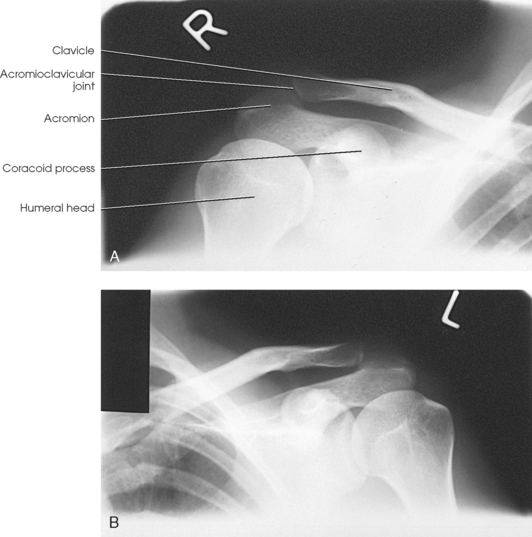

Alexander1 suggested that AP and PA axial oblique projections be used in cases of suspected AC subluxation or dislocation. Each side is examined separately.

• Have the patient place the back against the vertical grid device and sit or stand upright.

• Center the affected shoulder under examination to the grid.

• Adjust the height of the IR so that the midpoint of the film is at the level of the AC joint.

• Adjust the patient’s position to center the coracoid process to the IR (Fig. 5-58).

• Directed to the coracoid process at a cephalic angle of 15 degrees (Fig. 5-59). This angulation projects the AC joint above the acromion.

Structures shown: The resulting image shows the AC joint projected slightly superiorly compared with an AP projection (Fig. 5-60).